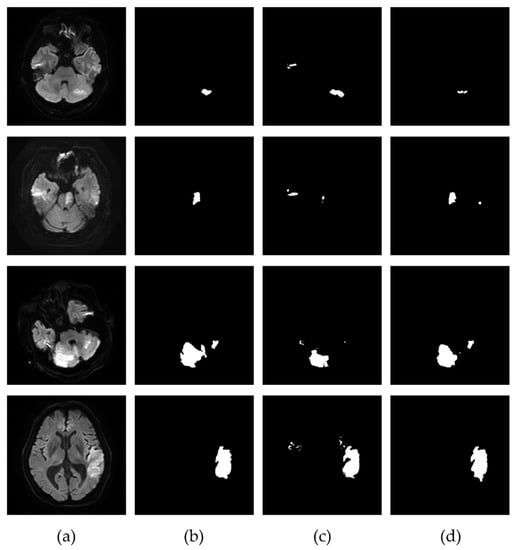

3.2. Extraction of the Infarcted Regions